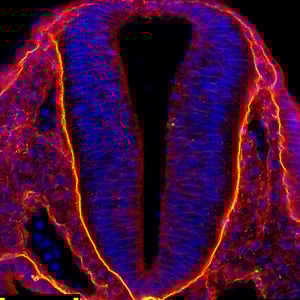

Neural tube development